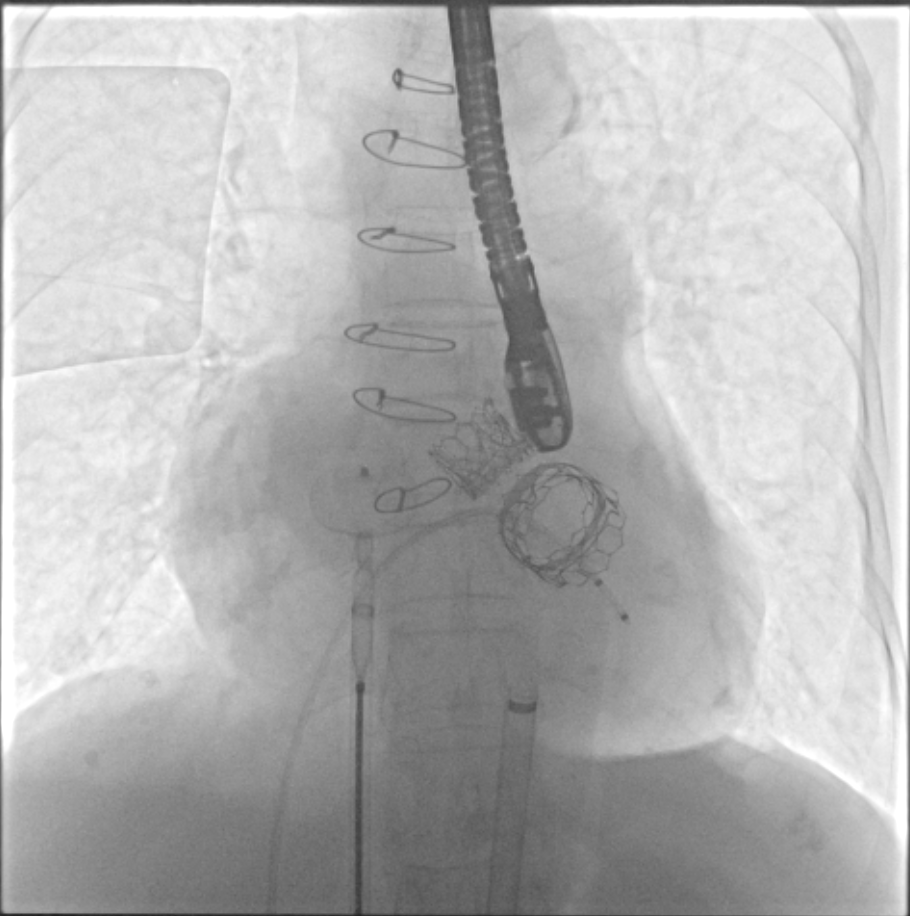

TMVR 术后房间隔封堵

在经过术前CTA评估测量等检查后,正式手术在珠海市人民医院医疗集团的百级层流复合手术室内进行,在林阿姨全麻的情况下使用食道超声及X线监测指引,经过3小时的紧张手术,双瓣中瓣手术最终成功完成。

经过充分的术前食道超声及心脏CTA的评估,团队一致选择目前国际上瓣中瓣(Valve in Valve)技术使用最多最成熟的器械——Edwards SAPIEN3瓣膜。与林阿姨及其家属充分沟通后,在经验丰富的王焱院长的指导下,珠海市人民医院结构性心脏病团队决定为林阿姨同期进行主动脉瓣及二尖瓣的双瓣膜置换,采用的方案是先经股动脉途径为其行主动脉瓣的瓣中瓣植入(VinV TAVR),然后经股静脉途径,穿刺房间隔后,行二尖瓣的瓣中瓣植入(VinV TMVR),视情况对房间隔穿刺后的缺损进行封堵。